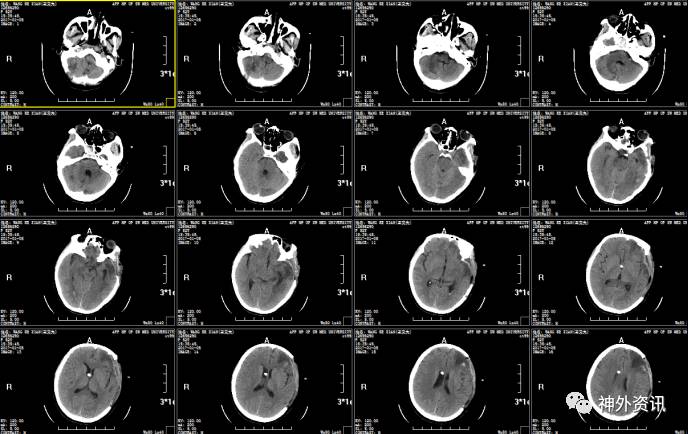

2017.01.03:侧脑室外引流术后第10天,患者意识呈昏睡,生命体征平稳,脑室引流管通畅,引流清亮脑脊液140ml,双瞳等大形圆直径2.5mm,光反射迟钝,予以关闭血浆引流管48h后复查头颅CT。

2016.01.06:复查头颅CT,关闭脑室血浆引流管后无脑积水表现,予以拔除血浆引流管。

患者出院时神志清楚,吐词欠清,双瞳等大形圆,直径约2..5mm,光反射灵敏,气管切口愈合良好,心肺腹(-),四肢肌力5级,肌张力不高,病理征(-),脑膜刺激征(-)。